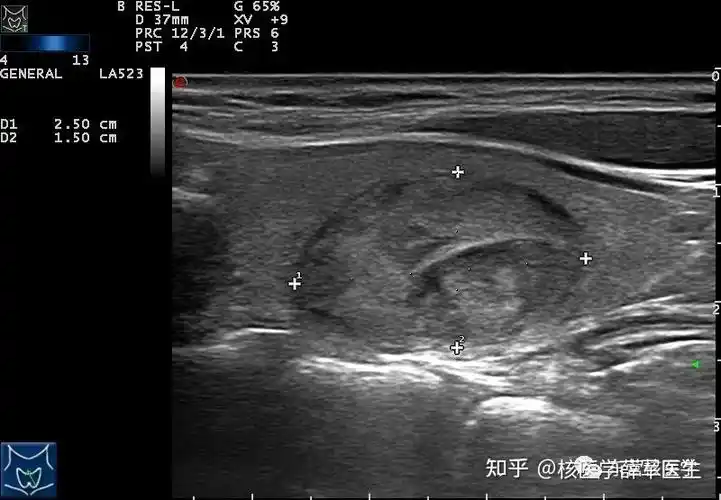

甲状腺结节超声报告解读